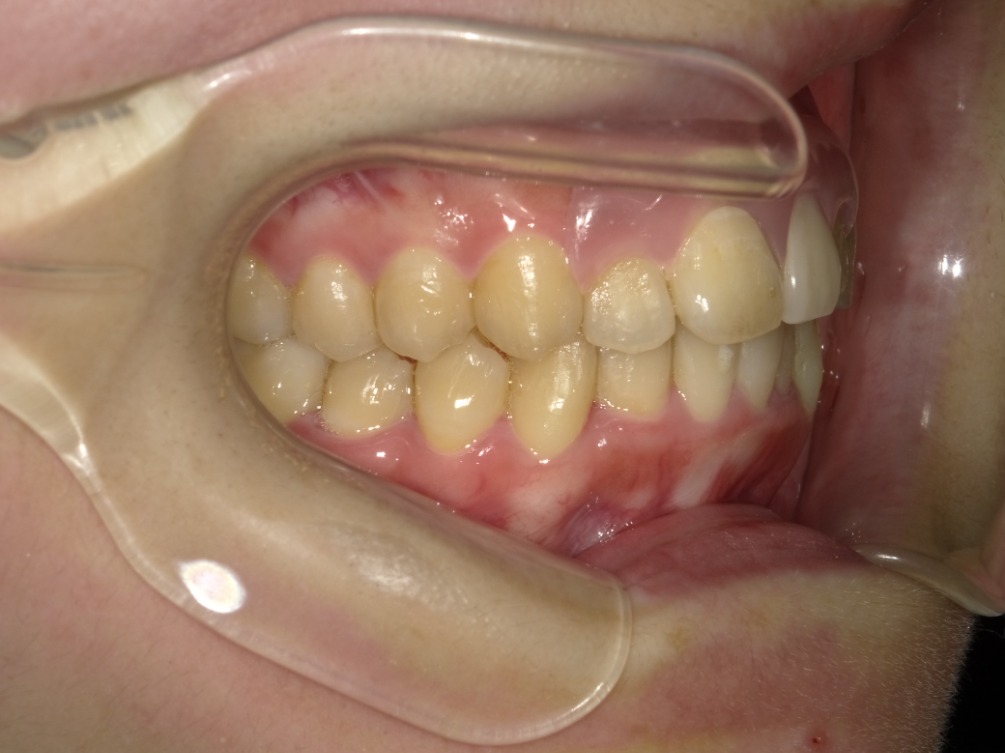

正面

| 治療内容 | インビザライン 全顎〈抜歯あり〉 |

| 治療詳細 | 叢生や交叉咬合を整えるために、歯の表面にアタッチメント(白い突起)をつけ、IPR(歯と歯の間を削る)を行いました。 また、顎間ゴムと呼ばれる引っ掛けるゴムの補助装置も用いて治療を行いました。 抜歯を1本して治療を行いました。該当部分は義歯を使用しています。 |

| 患者情報 | 20代 女性 デンタルモニタリング使用 |

| 主訴 | 歯のがたつき 一部分だけかみ合わせが反対 |